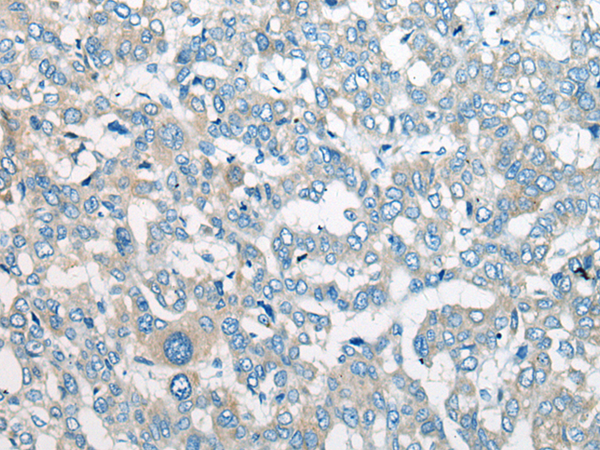

The image is immunohistochemistry of paraffin-embedded Human liver cancer tissue using P13067(CEP170 Antibody) at dilution 1/25. (Original magnification: ×200) |